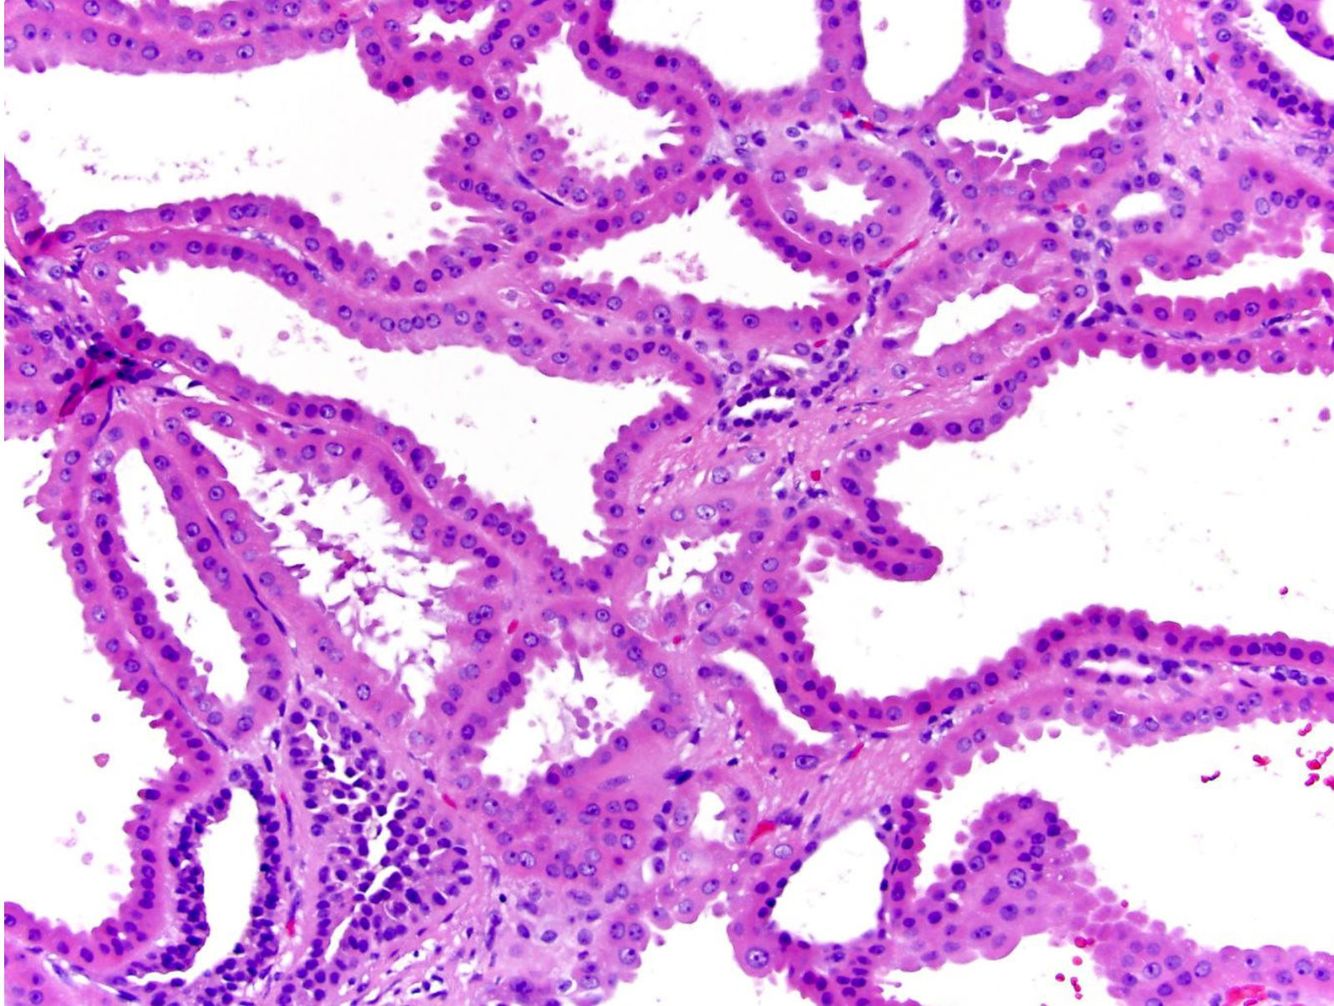

Clear cell papillary renal cell carcinoma

Low-grade clear cell neoplasm with a papillary or tubular architecture. Features include clear cells with small, dense, dark nuclei, cells arrarnged on delicate fibrovascular cores or packed into tight tubules, and may show cystic degeneration. Tumors are often small and well-circumscribed or encapsulated.